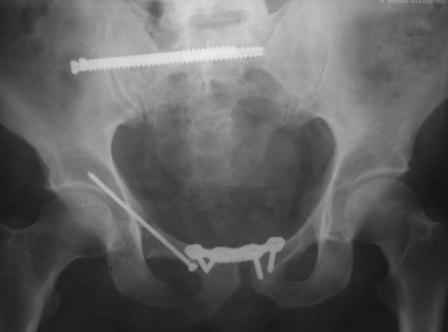

в архиве нашел подобный случай

С Уважением А.Миронов(Новокузнецк)

Уважаемый коллега! Огромное спасибо за рекомендации и иллюстрации! Задний комплекс, а точнее КПС не стал фиксировать т.к. само сочленение и суставная поверхность крестца целое, на кт-срезе имеет место краевой перелом и то не завершенный, учитывая что передняя связка КПС целая (а она сами знаете мошная)не стали фиксировать и клинический пациент не регировал, только КТ. Еще на Ваших фото винты вошли через кортикальный слой или ближе к перелому, а у нас вход в лон получилось прямо с мыса симфиза, т.е. перелом слева, винт зашел справа налево. Или это не принципиально?. С уважением Ерсин Жунусов.

положение и точка введения винта, при фиксации перелома горизонтальной ветви лонной кости и возможно acetabulum, определяется её анатомией. Корректная позиция и точка введения в приложенных картинках из руководства по внутреннему остеосинтезу.

С Уважением А.Миронов

1.jpg

64KB (66029 bytes)